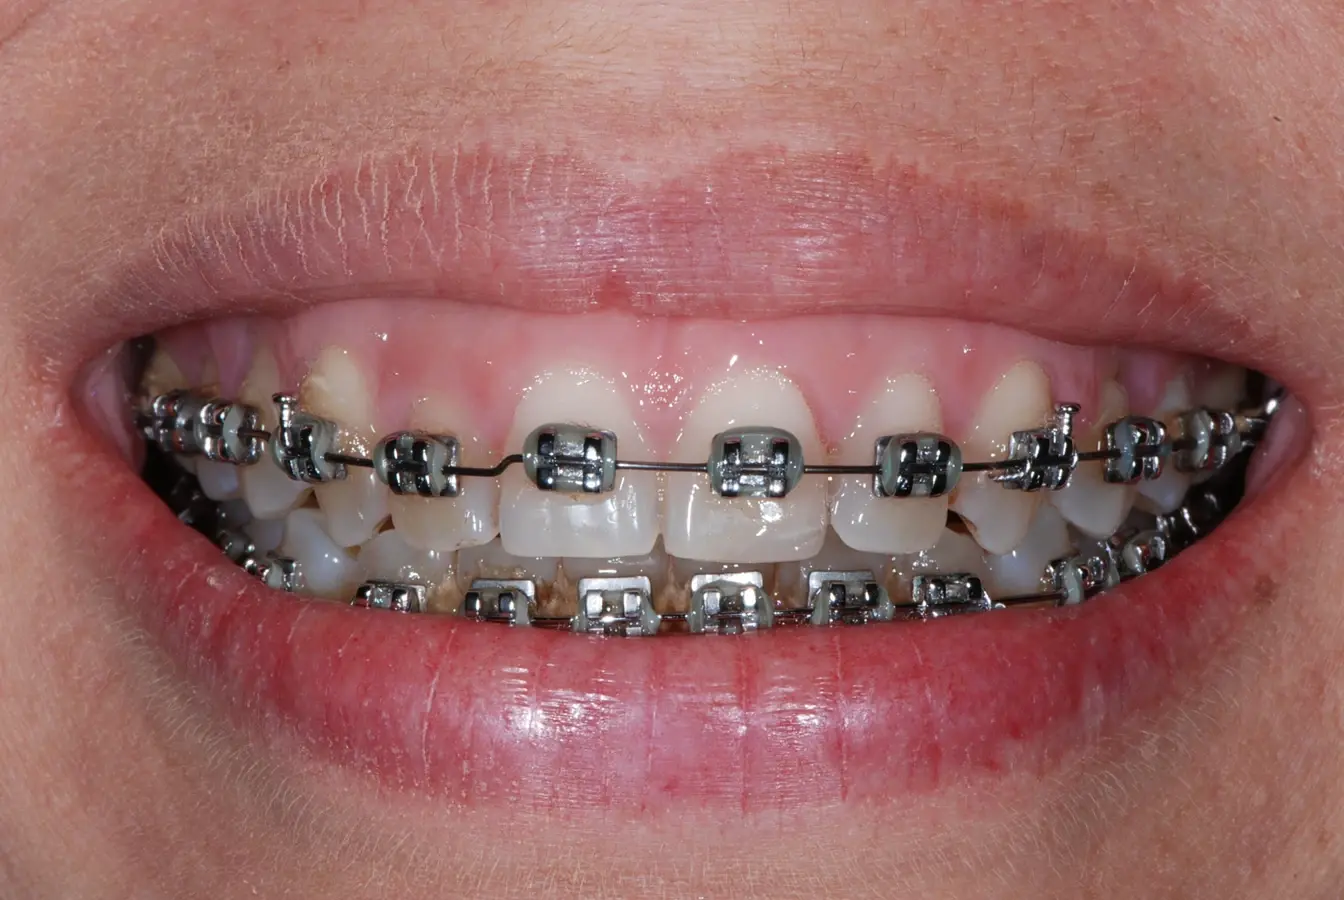

Las manchas y el oscurecimiento de los dientes son un efecto secundario temporal común del tratamiento de ortodoncia convencional con brackets, que se debe a la dificultad de los pacientes para mantener los dientes limpios durante el tratamiento. Los materiales utilizados en ortodoncia fija crean puntos de acumulación de placa, que pueden provocar la formación de precursores de manchas blancas, tinciones, caries y periodontitis1. Con el paso del tiempo, el contacto y la cantidad de la placa dental sobre la superficie dental aumenta, lo que puede irritación gingival, inflamación, hemorragia gingival y gingivitis2.

En el maxilar superior se observan surcos pigmentados en los elementos 1.4, 1.5, 2.4, 2.5 (Fig. B).

En el maxilar inferior se observa presencia de caries en los elementos 3.7, 4.7, también se observa restauraciones oclusales con amalgama en los elementos 3.6 y 4.6 (Fig. C).

Varios estudios microbiológicos que comparan la ortodoncia fija con la tecnología de alineadores indican una disminución significativa de la placa bacteriana con el tratamiento con alineadores debido a que los pacientes pueden realizar su higiene oral de forma normal, ya que tienen acceso a todas las superficies dentales. En cambio, los pacientes bajo tratamiento de ortodoncia convencional suelen declararse insatisfechos con el color de sus dientes debido al difícil manejo de la higiene bucal, que puede resultar en decoloración dental.

Los factores que contribuyen a la aparición de manchas en la superficie externa de los dientes son una higiene bucal deficiente, el tabaquismo o la ingesta de bebidas como café o vino. En casos aislados de pacientes con ortodoncia, el color dental puede alterarse como resultado de complicaciones derivadas de necrosis o hiperemia del tejido pulpar. Por ello, muchos pacientes de ortodoncia buscan un tratamiento de aclaramiento dental para mejorar la estética y su sonrisa. Estos dispositivos removibles de ortodoncia permiten mejorar la salud bucal y minimizan la aparición de lesiones blancas debido a la descalcificación del esmalte, lo cual es un hallazgo clínico común en casos de ortodoncia fija1,2,3.